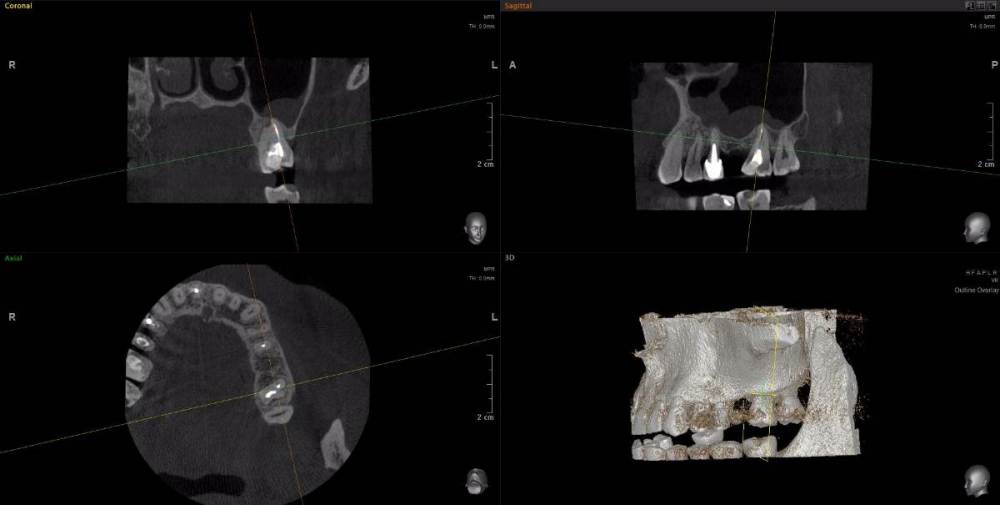

wladdX Опубликовано 15 апреля, 2021 Поделиться Опубликовано 15 апреля, 2021 Несколько скриншотов из вашей КЛКТ. Зуб 25: Зуб 27: Правая сторона: 1 Ссылка на комментарий

red_butler Опубликовано 16 апреля, 2021 Поделиться Опубликовано 16 апреля, 2021 1.5 1.6 перелечивать, 2.4 похоже кариес корня, нужно смотреть очно, 2.5 парадонтологическое поражение, смотреть очно, 2.6 ревизия корневых каналов Ссылка на комментарий